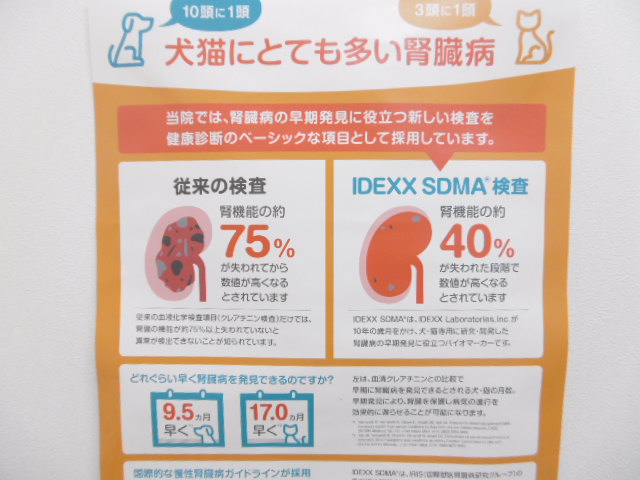

腎機能検査で一般的な血液検査といえば『BUN(尿素窒素)』『クレアチニン』です。一般的な健康診断に必ず入っている馴染みのある検査項目です。2つ共に動物の状態を把握しやすい優れた項目ではありますが、腎臓病(腎不全)の早期発見については、より優れた検査項目が数年前から実施されています。それが『SDMA』です。

SDMAは『対称性ジメチルアルギニン』の略です。アミノ酸のアルギニンがジメチル化された物質です。SDMAのほぼ全てが腎臓の濾過によって排泄されるため腎機能の指標となります。SDMAは『クレアチニン』よりも早期に腎臓病(腎不全)の発見を出来る可能性のある事がわかっています。具体的に犬で9.5か月、猫で17か月も早いと言われています。特に猫ちゃんでは腎臓病の早期発見は大事です。

つまりSDMAを検査する事で腎臓病を早期発見し、進行を遅らせるための早期治療を積極的に行う事が可能です。SDMAについて詳しく知りたい方は以下のバナーをクリックしてみてください。